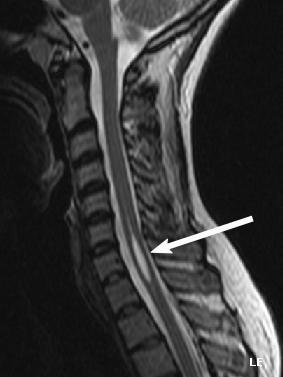

| An idiopathic syrinx | |

Physicians now use magnetic resonance imaging (MRI) to diagnose syringomyelia. The MRI radiographer takes images of body anatomy, such as the brain and spinal cord, in vivid detail. This test will show the syrinx in the spine or any other conditions, such as the presence of a tumor. MRI is safe, painless, and informative and has greatly improved the diagnosis of syringomyelia.[14][15][16][17][18][19][20][21][22][23][24][25]

The possible causes are trauma, tumors, and congenital defects. It is most usually observed in the part of the spinal cord corresponding to the neck area. Symptoms are due to spinal cord damage and include pain, decreased sensation of touch, weakness, and loss of muscle tissue. The diagnosis is confirmed with a spinal CT, myelogram or MRI of the spinal cord. The cavity may be reduced by surgical decompression.